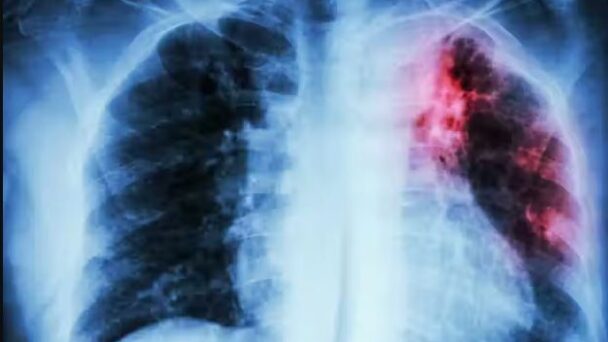

El Minsa también puso en marcha en abril pasado un programa de capacitación a profesionales del sector para poder detectar la tuberculosis mediante rayos X con inteligencia artificial (IA).

Perú es uno de los países con mayor cantidad de casos de tuberculosis en Latinoamérica, pues cada año se diagnostican alrededor de 27.000 nuevos contagios de esta enfermedad infecciosa, y 17.000 de tuberculosis pulmonar frotis positivo, según cifras oficiales. EFE